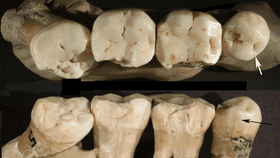

Frayer and Radov?i? studied four Neanderthal teeth under a microscope, picking up signs of grooves consistent with the use of toothpicks, along with what dentists call occlusal wear, the loss of material from teeth rubbing against each other.

In the Bulletin of the International Association for Paleodontology (yes seriously, that is a twice-yearly journal) the pair report that previous studies on the same teeth identified where in the mouth they came from. All four had toothpick grooves, but these were much deeper on an M3 molar and premolar. Those teeth also showed signs of abnormality, with the premolar rotated and the M3 partially impacted.

Similar grooves have been found on teeth from other human species, dating back 1.8 million years, but the fact the grooves were so much deeper on the displaced teeth is the most powerful evidence yet that they represent a response to toothache, ie an early form of dentistry. The finding follows the discovery of a Spanish Neanderthal who ate aspirin and Penicillium mold when suffering a dental abscess.